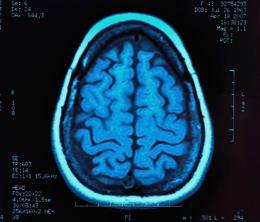

Researchershave used the scan to look at the surface area and thickness of different parts of a child’s cerebral cortex as well as the shifting size. They measure against normal sizes at both the six and twelve-monthmarks of a child’s development.

Once researchers had conducted the scans at the six and twelve-monthmarks, the results were then inputtedinto a computer program. The computer used two observations to determine its prediction.

First – Infants who develop autism by age two appear to undergo relatively high brain-surface growth between ages six months and one year.

Second – High brain surface area growth in the first year of life is linked to a higher overall brain size in the second year of life.